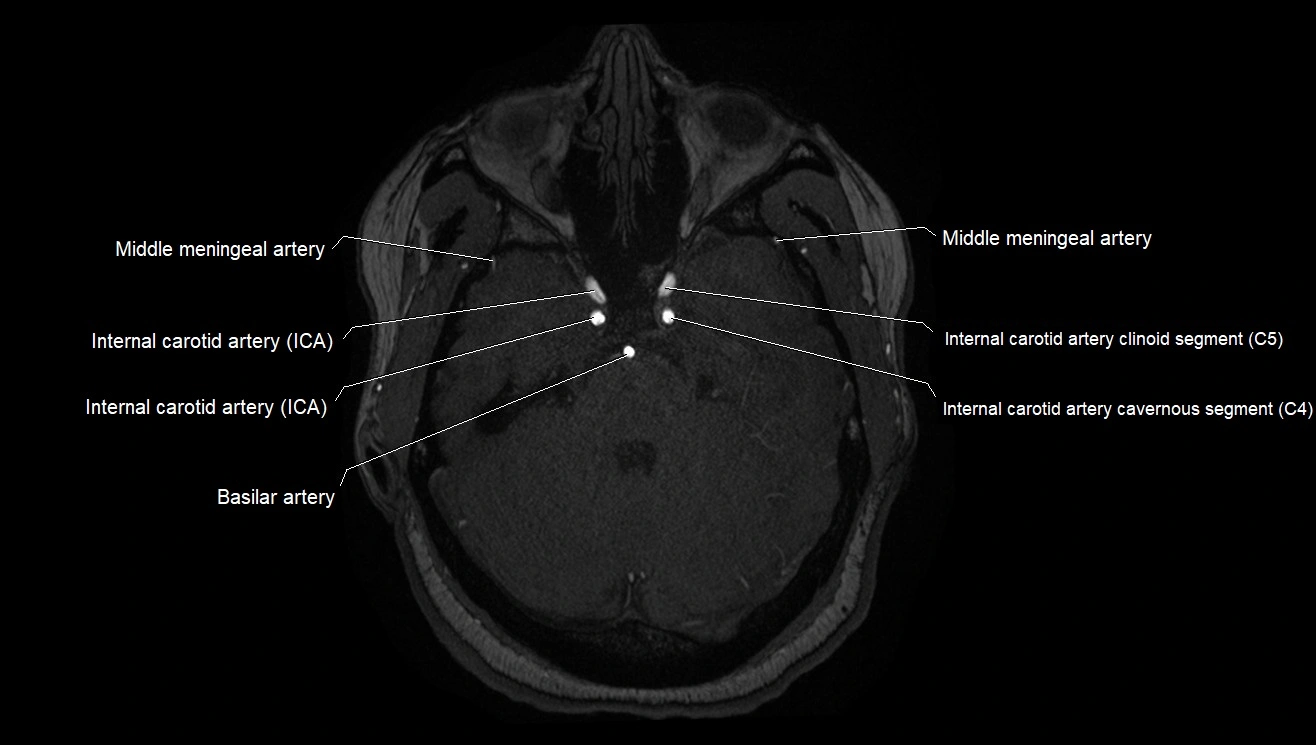

CT images

image